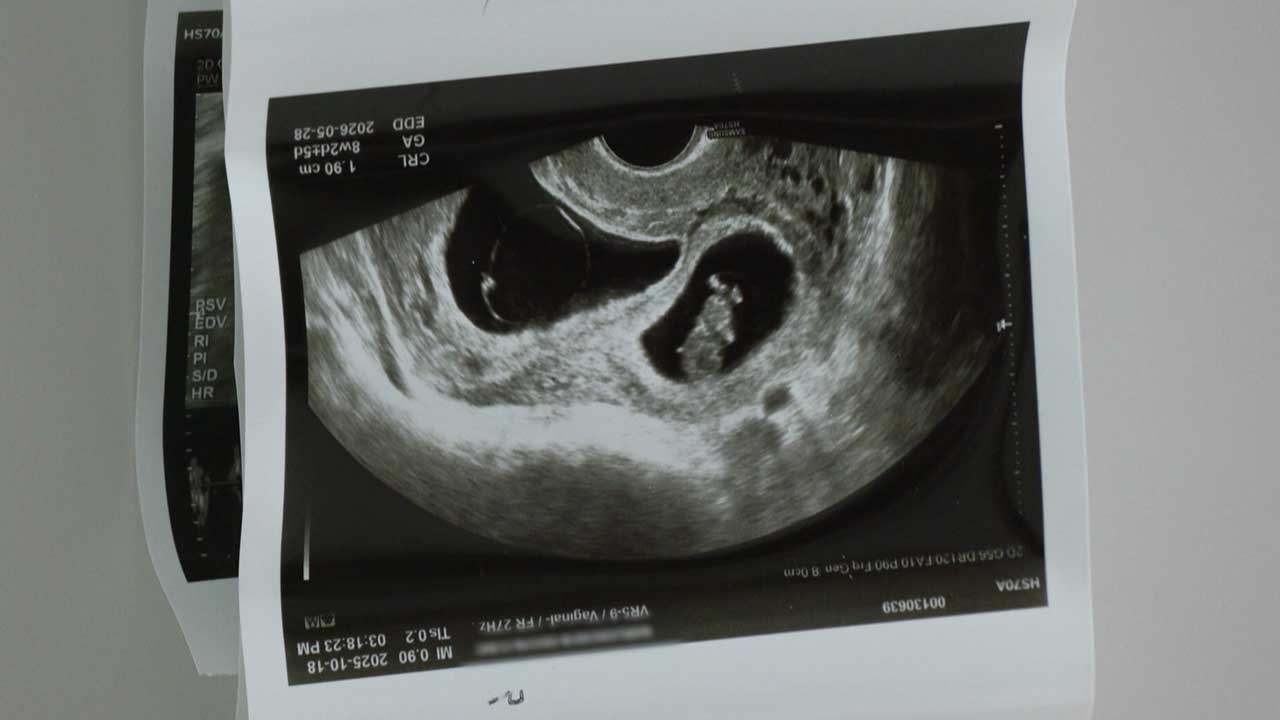

그날 아침으로 돌아가봅니다. 지난달 7일, 추석 이튿날이었습니다. 경기도 양주시에 있는 집에서 종희 씨는 노트북으로 '쌍둥이 카시트'를 검색하고 있었습니다. 뭐가 그리 좋은지 소년 같이 웃고 있었다고 합니다. 아내를 보고는 "아기들을 어서 빨리 보고 싶다"고 속삭였습니다. 종희 씨가 생각해 둔 아기들 이름은 '강', '단'이었습니다. 다치지 않고 튼튼하게 자랐으면 하는 바람뿐이었다고 합니다. 신혼집 냉장고 한켠에는 쌍둥이 태아 초음파 사진이 붙어있었습니다. 그가 살아서 본 쌍둥이의 마지막 모습입니다.